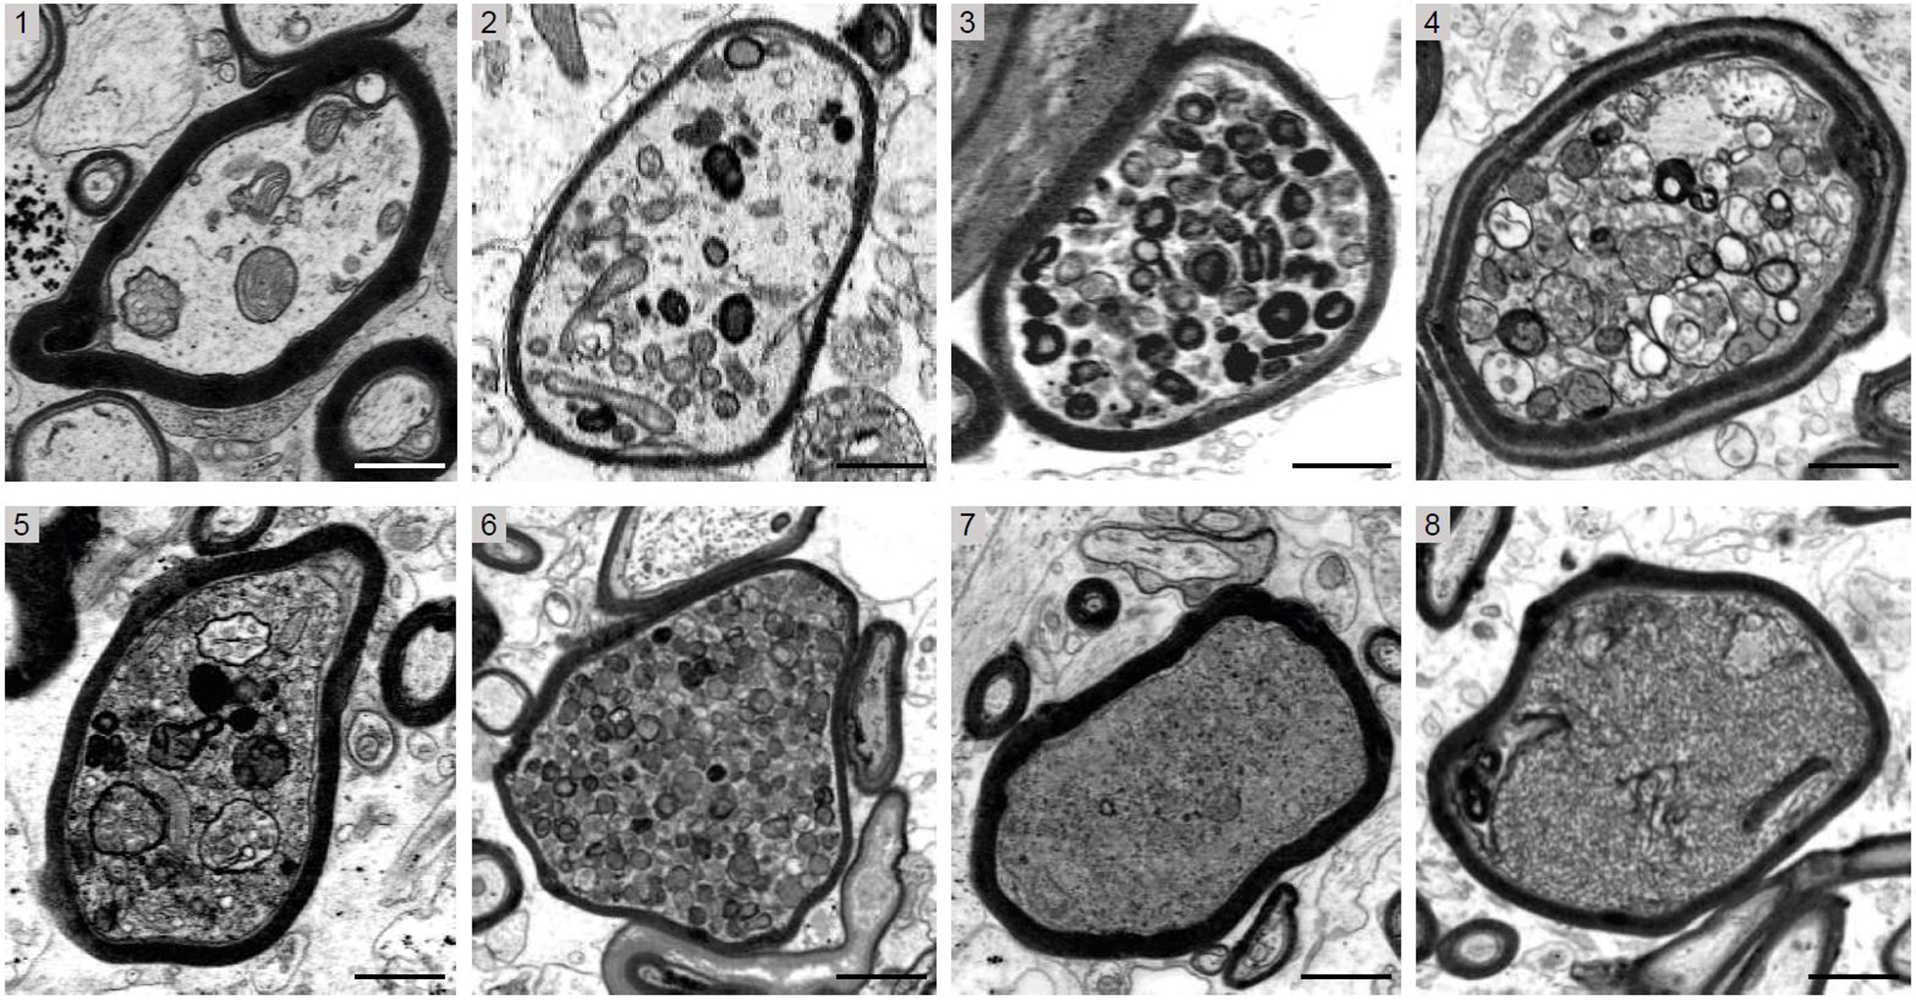

“When oligodendrocytes are exposed to an acute inflammatory environment, they may lose their ability to support the axons, and myelin becomes a threat to the survival of the axons,” says Professor Klaus-Armin Nave from the Max Planck Institute for Multidisciplinary Sciences in Göttingen, Germany, describing the team’s research hypothesis that was formulated at the outset. To test their hypothesis, the researchers examined tissue samples from patients with multiple sclerosis, as well as various mouse models of this disease in order to experimentally simulate the autoimmune attack on myelin. For the first time, the researchers were able to demonstrate by electron microscopy in the tissue samples of the patients that irreversible damage almost always occurs in the axons that are still coated with myelin (see figure). Conversely, using genetically modified mouse models, the researchers were able to show that “naked” axons in an acute inflammatory region of the central nervous system are better protected from degeneration.